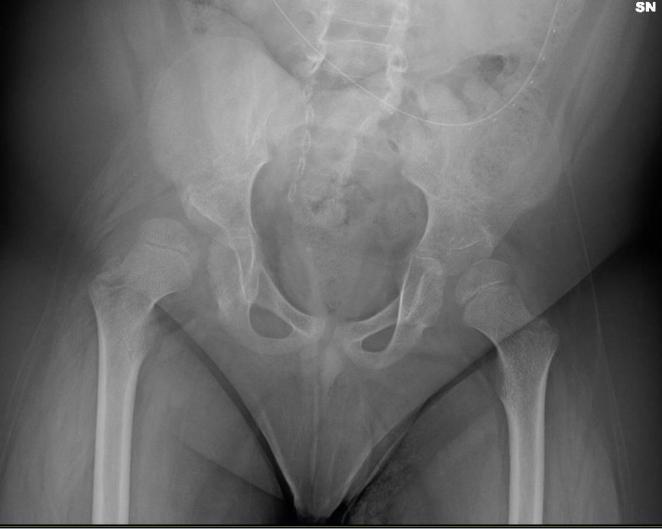

Paraparesis. Bilateral neurogenic clubfoot, surgically treated. Hip dislocation

The follow-up pelvic X-ray showed a superolateral subluxation of the right femur with deformation of the acetabular roof

The follow ray showed a superolateral subluxation of the right femur with deformation of the acetabular roof